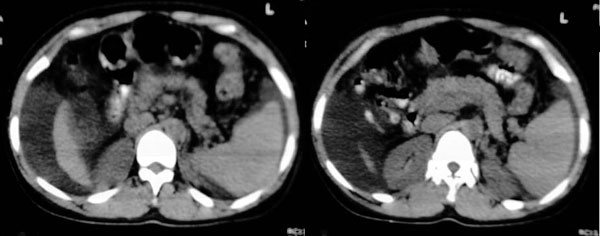

支持楼上各位老师的讨论,但还需要提醒楼主注意食管腹部,有可能是食道癌。再者就要怀疑是食管周围的病变,考虑是肿大的淋巴结。

肝脏体积缩小,左右肝比例失调,轮廓不规整,肝裂增宽,肝周见新月形液性密度影,脾脏增厚.应诊断为肝硬化,腹水,脾大.

肝脏体积变小,左右比例失调,右肝变小较剧,脾脏增厚,腹水征象明显考虑肝硬化、腹水